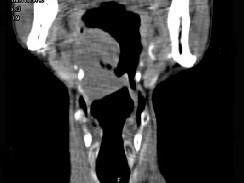

问题 男,74岁,咽喉部不适一年余,近两三个月咽喉疼痛,吞咽困难,CT如图所示,最可能诊断是 ( )

选项 A、声门下区癌 B、跨声门型癌 C、会厌癌 D、声带癌 E、喉癌

答案 C